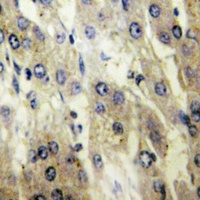

FATP5 Antibody

IF, IHC, WB

应用稀释比例:WB: 1:500-1:1000, IHC-P: 1:100-1:200, IF/ICC: 1:100-1:500